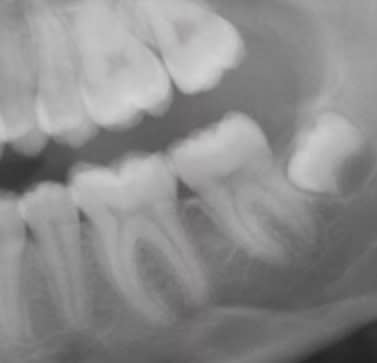

Je ne suis absolument pas d'accord avec l'extraction !

Cette dent est à redresser, cela ne devrait même pas se discuter.

Quand à parler de "galère", il suffit d'employer la bonne technique...

Un CT8 (ou même un simple CTO comme sur les photos jointes car elle n'est qu'enclavée) ) est le système de choix.

Daniel

Il n'est pas tant question de technique ou de faisabilité que d'intérêt final. Ce cas n'a rien à voir avec celui que tu présentes en panoramique, l'espace disponible n'est pas du tout le même.

Le CT8 est un très bel outil, élégant et efficace je trouve, que j'aimerais mettre en place au cabinet, mais il a ses indications et ne va pas miraculeusement créer de l'espace en distal... Ca me rappelle la petite phrase d'un de mes profs de fac, qui nous avait mis en garde en disant un quelque chose de ce genre : "attention, quand on a un marteau dans la main, on voit des clous partout !". J''appelle ça aussi le syndrôme Ikea : quand on rentre en magasin et qu'on récupère un ruban mètre, on a subitement envie de TOUT mesurer !